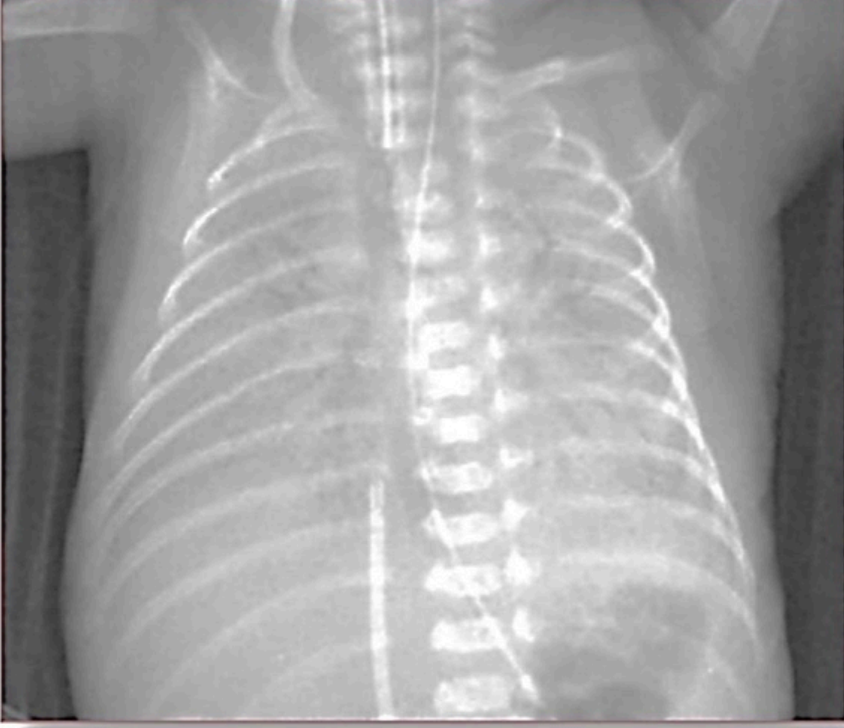

Preterm 29-weeks gestation C/S delivery showed severe respiratory distress soon after birth. This chest x-

ray was taken at age of 6 hours.

Q1: ground glass appearance, wide intercostal space.

Q2: Neonatal respiratory distress syndrome.

Q3: mechanical ventilation, give Surfactant for lungs maturation.

Xray findings

- White lung

- Air bronchogram

- Ground glass appearance

- low lung volume

What is your diagnosis? RDS

What is the definite treatment? Surfactant.